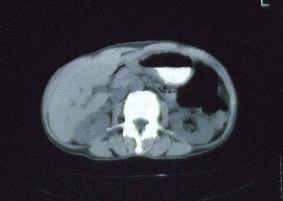

Caso de resección de patología gástrica de tipo inflamatoria que se presentó con hallazgos similares al cáncer avanzado

Enfermedad Inflamatoria - Ulcerativa/otros

estómago(región)/otros

TAC